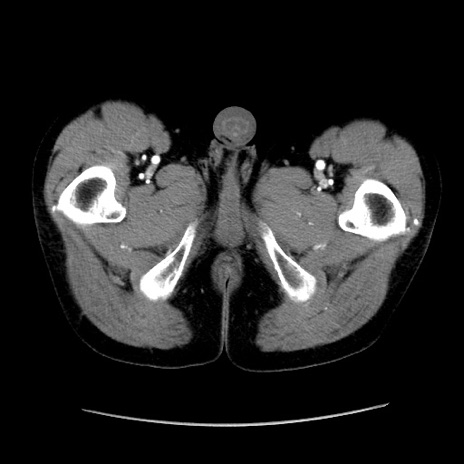

症例37(横断像)

【症例】40歳代 男性

【主訴】腹痛

【現病歴】4時間ほど前に電車に乗車中に臍部上より腹痛出現。徐々に増悪し起立困難となり、救急外来受診。生ものは数日食べていない。今朝お雑煮を食べた。

【身体所見】BT 36.8℃、BP 117/84mmHg、HR 91/min、SpO2 97%、苦悶様、腹部:臍上部広範囲圧痛あり、反跳痛±

【データ】WBC 8100、CRP 0.03